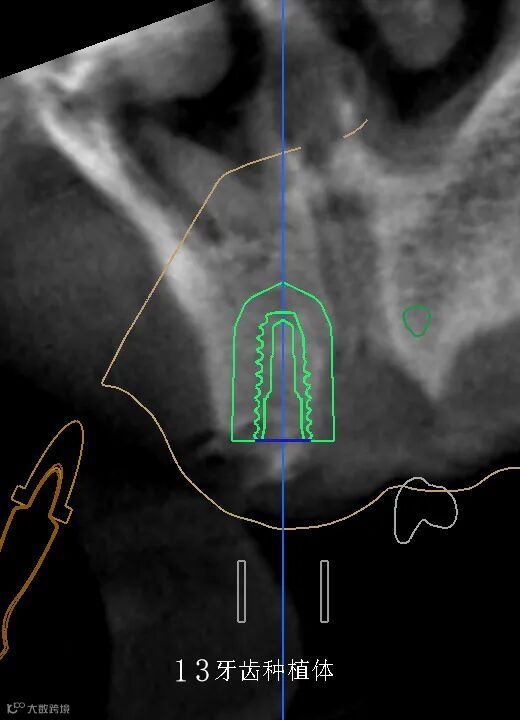

数字化种植手术规划与导板设计

精准——术前精确设计,术中精准控制,避免损伤重要的解剖结构,实现安全种植,以美学修复为导向,为永久修复牙位设计更理想、美观。